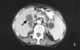

Courvoisier gallbladder

Courvoisier's law (or Courvoisier syndrome, or Courvoisier's sign or Courvoisier-Terrier's sign) states that in the presence of a palpably enlarged gallbladder and accompanied with mild jaundice, the cause is unlikely to be gallstones. Usually, the term is used to describe the physical examination finding of the right-upper quadrant of the abdomen. [Source: Wikipedia ]